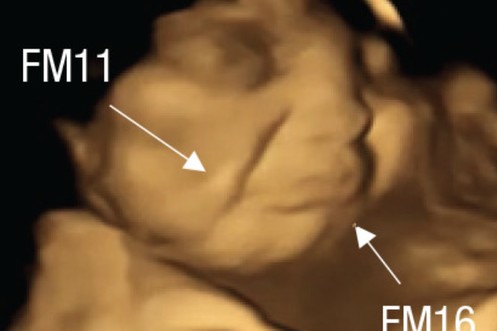

Ungeborene Kinder schneiden Grimassen, wenn die Mutter Federkohl isst